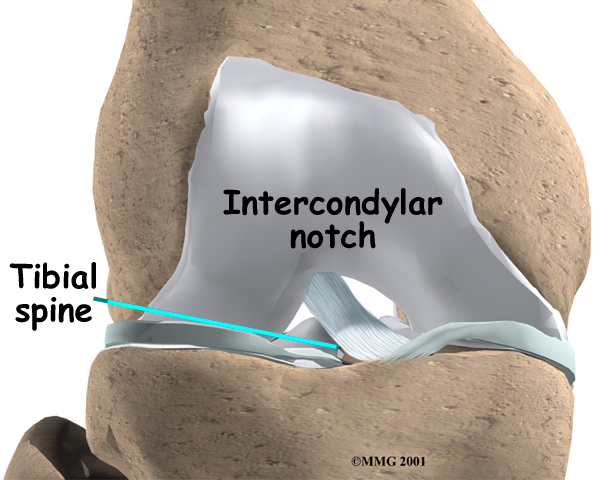

The ACL runs through a special notch in the femur called the intercondylar notch and attaches to a special area of the tibia called the tibial spine.

Tibial Spine